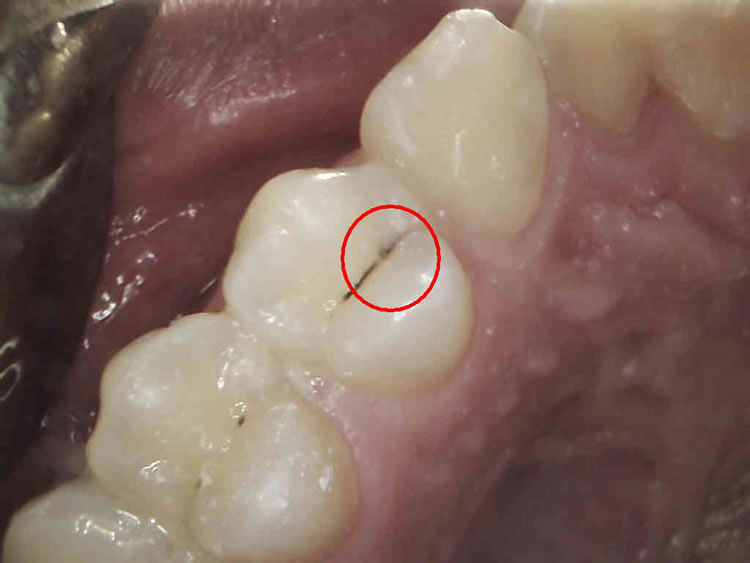

Karijes najčešće zahvaća zube na kojima se hrana lakše skuplja. Oblikom su najizloženiji kutnjaci i pretkutnjaci. Posebno su osjetljivi prostori između dva zuba koji su nedostupni za čišćenje četkicom za zube.

U početnoj fazi karijes je bijela mrlja koja zahvaća samo površinski sloj cakline i kao takav je praktički neosjetljiv. U uznapredovanoj fazi karijes prodire kroz caklinu i ulazi u dentin. Tada zub postaje osjetljiv na podražaje.

Vrlo često tada zub kavitira, uruši se i pacijent prepoznaje karijes kao rupu u zubu. Ako se karijes ni tada ne sanira, napreduje dublje i zahvaća zubnu pulpu. Tada dolazi do upale pulpe ili čak u jačim slučajevima do nekroze ili gangrene pulpe. Daljnjim napredovanjem dolazi do oteklina, jer se upalni proces širi u čeljusnu kost.